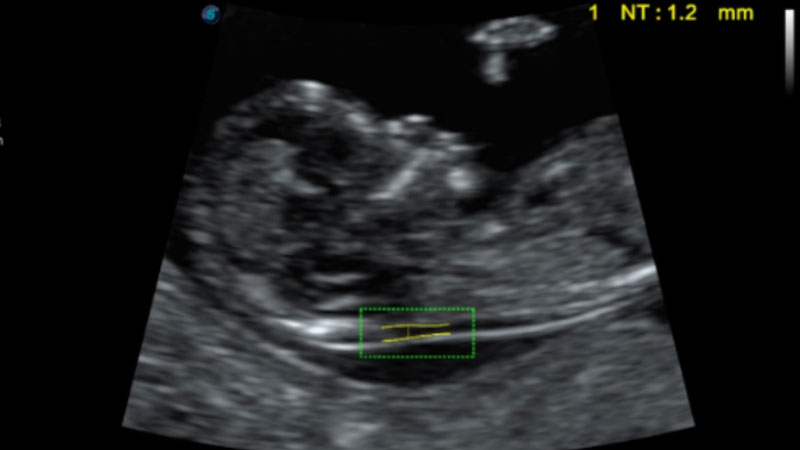

S-Fetus基于大數(shù)據(jù)深度學習算法,能夠幫助您在產(chǎn)前篩查過程中智能識別胎兒標準切面、自動測量并錄入報告。一個按鍵,即可智能、精準、高效地獲取胎兒生理指標,極大簡化您的產(chǎn)科檢查操作。

可快速對產(chǎn)科掃查切面完成胎兒生理學參數(shù)的自動測量,減少操作者按鍵次數(shù),大幅提升檢查效率。

自動識別頸項透明層并獲得NT值,為早孕胎兒畸形篩查提供有效測量工具,提高診斷效率和診斷信心。